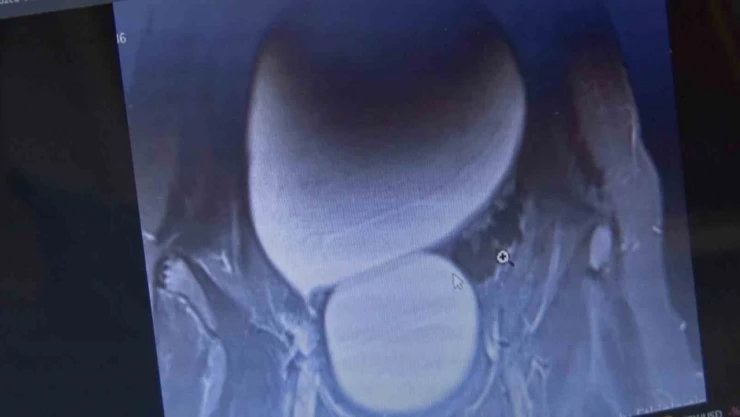

Sivas’ta yaşayan 12 yaşındaki N.B. şiddetli karın ağrıları ve düzensiz adet kanamaları şikayetiyle hastaneye başvurdu. Yapılan detaylı tetkikler sonucunda genç kızın karın bölgesinde yaklaşık 25 santimetre çapında adeta kavun büyüklüğünde bir kist olduğu tespit edildi. Medicana Sivas Hastanesi’nde Çocuk Cerrahisi Uzmanı Op. Dr. Mahmut Aluç tarafından gerçekleştirilen başarılı bir operasyonla, genç kızın sol yumurtalığında bulunan ve karaciğere kadar uzanan devasa kist içerisindeki 1.6 litre su boşaltılıp, başarıyla çıkarıldı. Sağlığına kavuşan genç kız taburcu edildi.

Çocuk Cerrahisi Uzmanı Op. Dr. Mahmut Aluç, kisttin içerisinden yaklaşık 1.6 litre sıvı boşaltıldığını söyleyerek, “ Karın ağrısı, düzensiz adet şikayetiyle bize geldi. Dışarıda yapan tetkiklerde ve bizde yapılan tetkiklerinde karın içerisinde yaklaşık yirmi beş santimetrelik çapında bir kitli kitle tespit ettik. Burada da tetkiklerimize tekrar baktığımızda sol över kökenli bir kisttik yapı olduğunun farkına vardık. Gerekli incelemeleri yaptıktan sonra ve ailenin onayını aldıktan sonra hastayı operasyona aldık. Karaciğere kadar uzanan bir kisttik yapımız vardı. Onun içerisinde yaklaşık 1.6 litre sıvı boşalttık. Over dokusunu, yumurtalık dokusunu koruyarak kisti tamamen eksize ettik. Hastamızı şifayla taburcu ettik. Patoloji sonucumuz da iyi huylu olarak geldi” dedi.